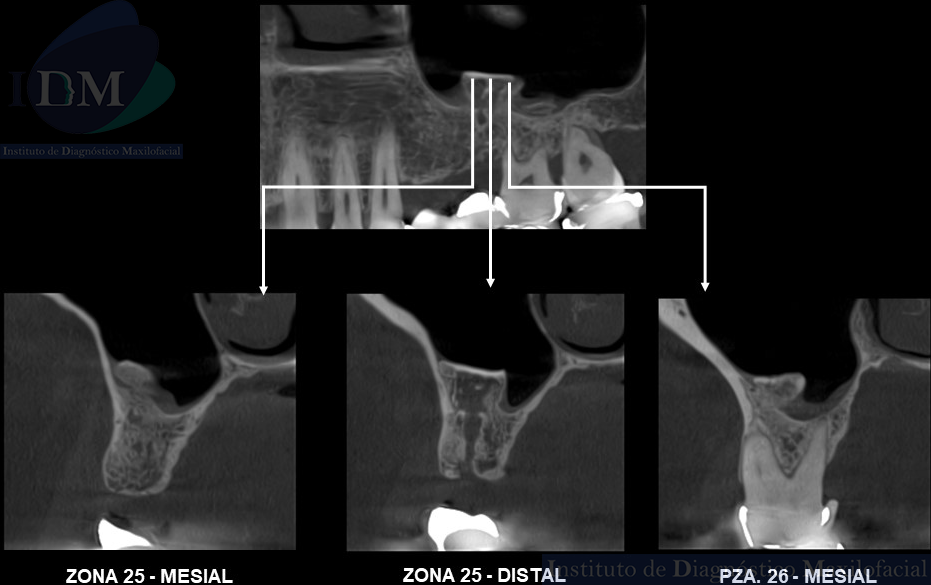

A la evaluación de la tomografía computarizada de haz cónico (TCHC) en los cortes axiales, transaxiales y en la reconstrucción 3D se observa una estructura ovalada hiperdensa heterogénea con contenidos mixtos irregulares localizada en piso del seno maxilar izquierdo con extensión hacia el antro sinusal. Además, en las imágenes tangenciales se observa la presencia de un antrolito adyacente a nivel de la pieza 26.

CORTES TANGENCIALES